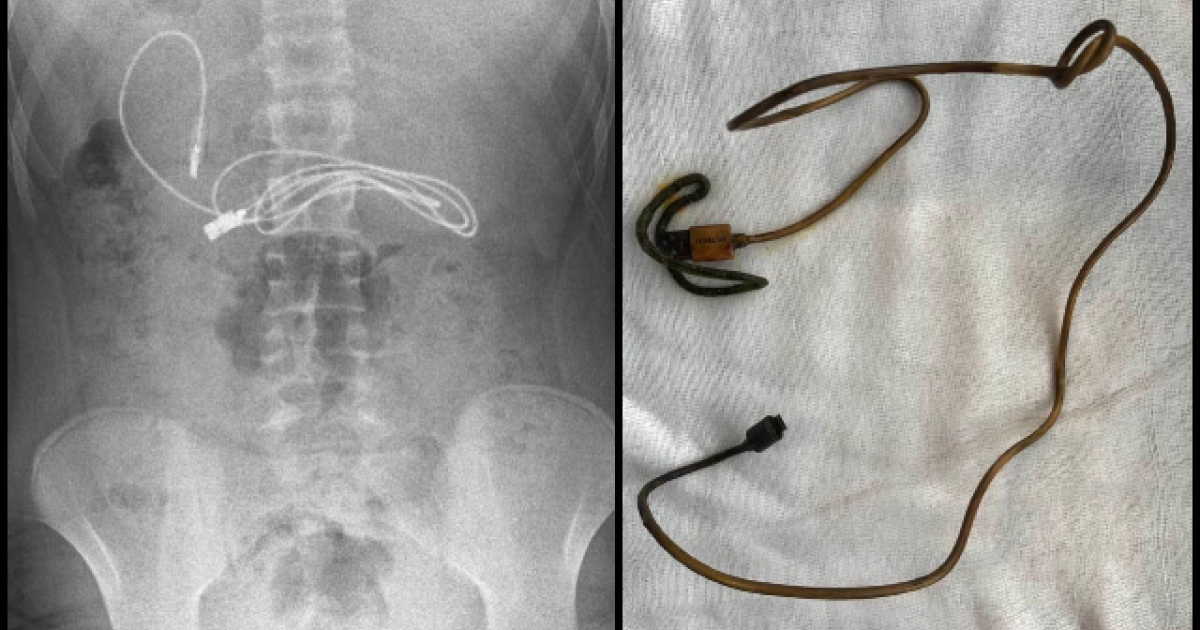

Το αγόρι από τον Ντιγιαρμπακίρ μεταφέρθηκε εσπευσμένα από την οικογένειά του στο νοσοκομείο έπειτα από παράπονα για ναυτία και πόνους στο στομάχι. Μια ακτινογραφία έδειξε ότι είχε μέσα στο στομάχι του έναν φορτιστή.

Όταν έφτασε ο επικεφαλής του τμήματος παιδιατρικής γαστρεντερολογίας και η ομάδα του, απάλλαξαν το παιδί από τον φορτιστή με τη μέθοδο της ενδοσκόπησης. «Δυσκολευτήκαμε να αφαιρέσουμε το καλώδιο, καθώς το ένα άκρο του είχε περάσει στο λεπτό έντερο», είπε ο Dogan.

Ο φορτιστής είχε μήκος περίπου ένα μέτρο ενώ σε κάποιο σημείο είχε έναν κόμπο, κάτι που δυσκόλεψε ακόμα περισσότερο την αφαίρεση του. Παραμένει ακόμα πώς και γιατί ο 15χρονος έφαγε τον φορτιστή.